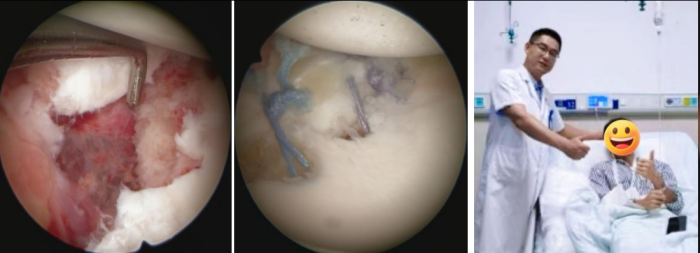

“患者入院后,经过详细的体格检查和影像学评估,发现他的肩胛盂前下方的盂唇撕裂了。更严重的是,巨大的脱位力量竟然将肩胛盂的边缘撞击成粉碎性骨折。”91短视频

运动医学科副主任、主任医师余敏介绍,医学上把这种情况称之为Bony Bankart损伤。Bony Bankart损伤是一种常见的肩关节损伤,通常由肩关节前脱位引起,涉及关节盂前下方的撕脱性骨折及盂唇、韧带复合体的损伤。“刘江目前肩胛盂的边缘缺了一块,会导致关节不稳,肱骨头很容易滑出去,轻微外力就可能脱位。”

术前CT示肩胛盂前下方骨折(Bony bankart损伤)

考虑到患者年轻且有强烈的运动需求,运动医学科团队为他实施了关节镜下微创修复手术。通过三个几毫米的小切口,精准地将撕脱的骨折块和盂唇组织复位到原位,并将它们牢固地重新固定在了肩胛盂上,恢复了肩关节稳定性结构,患者术后恢复良好,现已进入个性化的康复阶段。

关节镜下微创修复手术,患者术后恢复良好